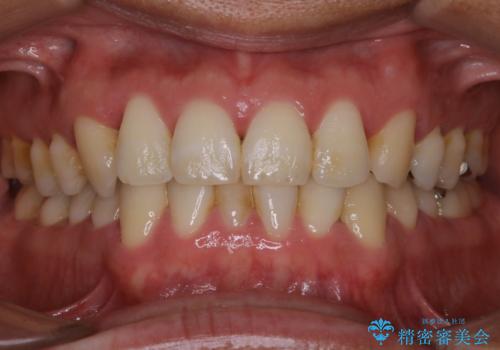

全体的な治療の開始前に着色取り